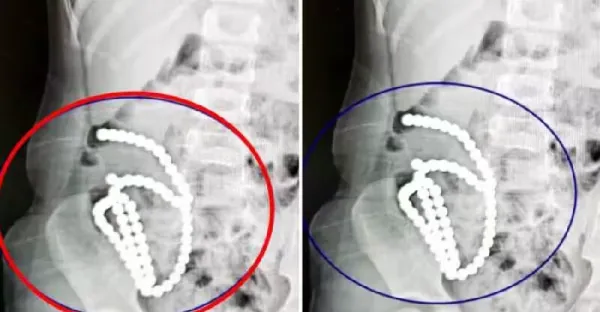

4歲妹照X光驚見「肚子整串白珠珠」媽證實哥哥在玩!醫嘆:一輩子毀了…

呂純弘 • 690次觀看